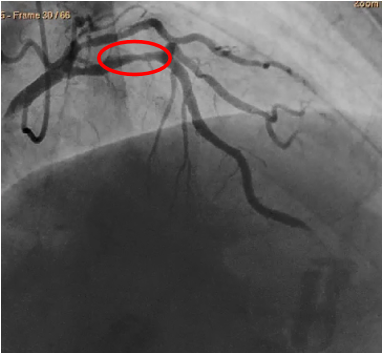

冠状动脉血管造影

LM未见异常;pLAD 50%狭窄,p-mLAD 50%~75%狭窄长病变;

LCX开口25%狭窄,dLCX 100%闭塞,可见LCX自身侧枝循环形成。

dRCA狭窄25%,PL狭窄25%;右冠优势型。

行LAD FFR检查,应用Medtronic 6F EBU 3.75导引导管达左冠开口,送入ST. Jude Pressurewire Certus压力导丝至LAD远端,静脉泵入ATP 140ug/kg.min 150秒行FFR测量,结果LAD FFR值0.69。与患者及家属沟通后,行LAD介入治疗。

介入治疗术前、术后对比

术前50%~75%狭窄